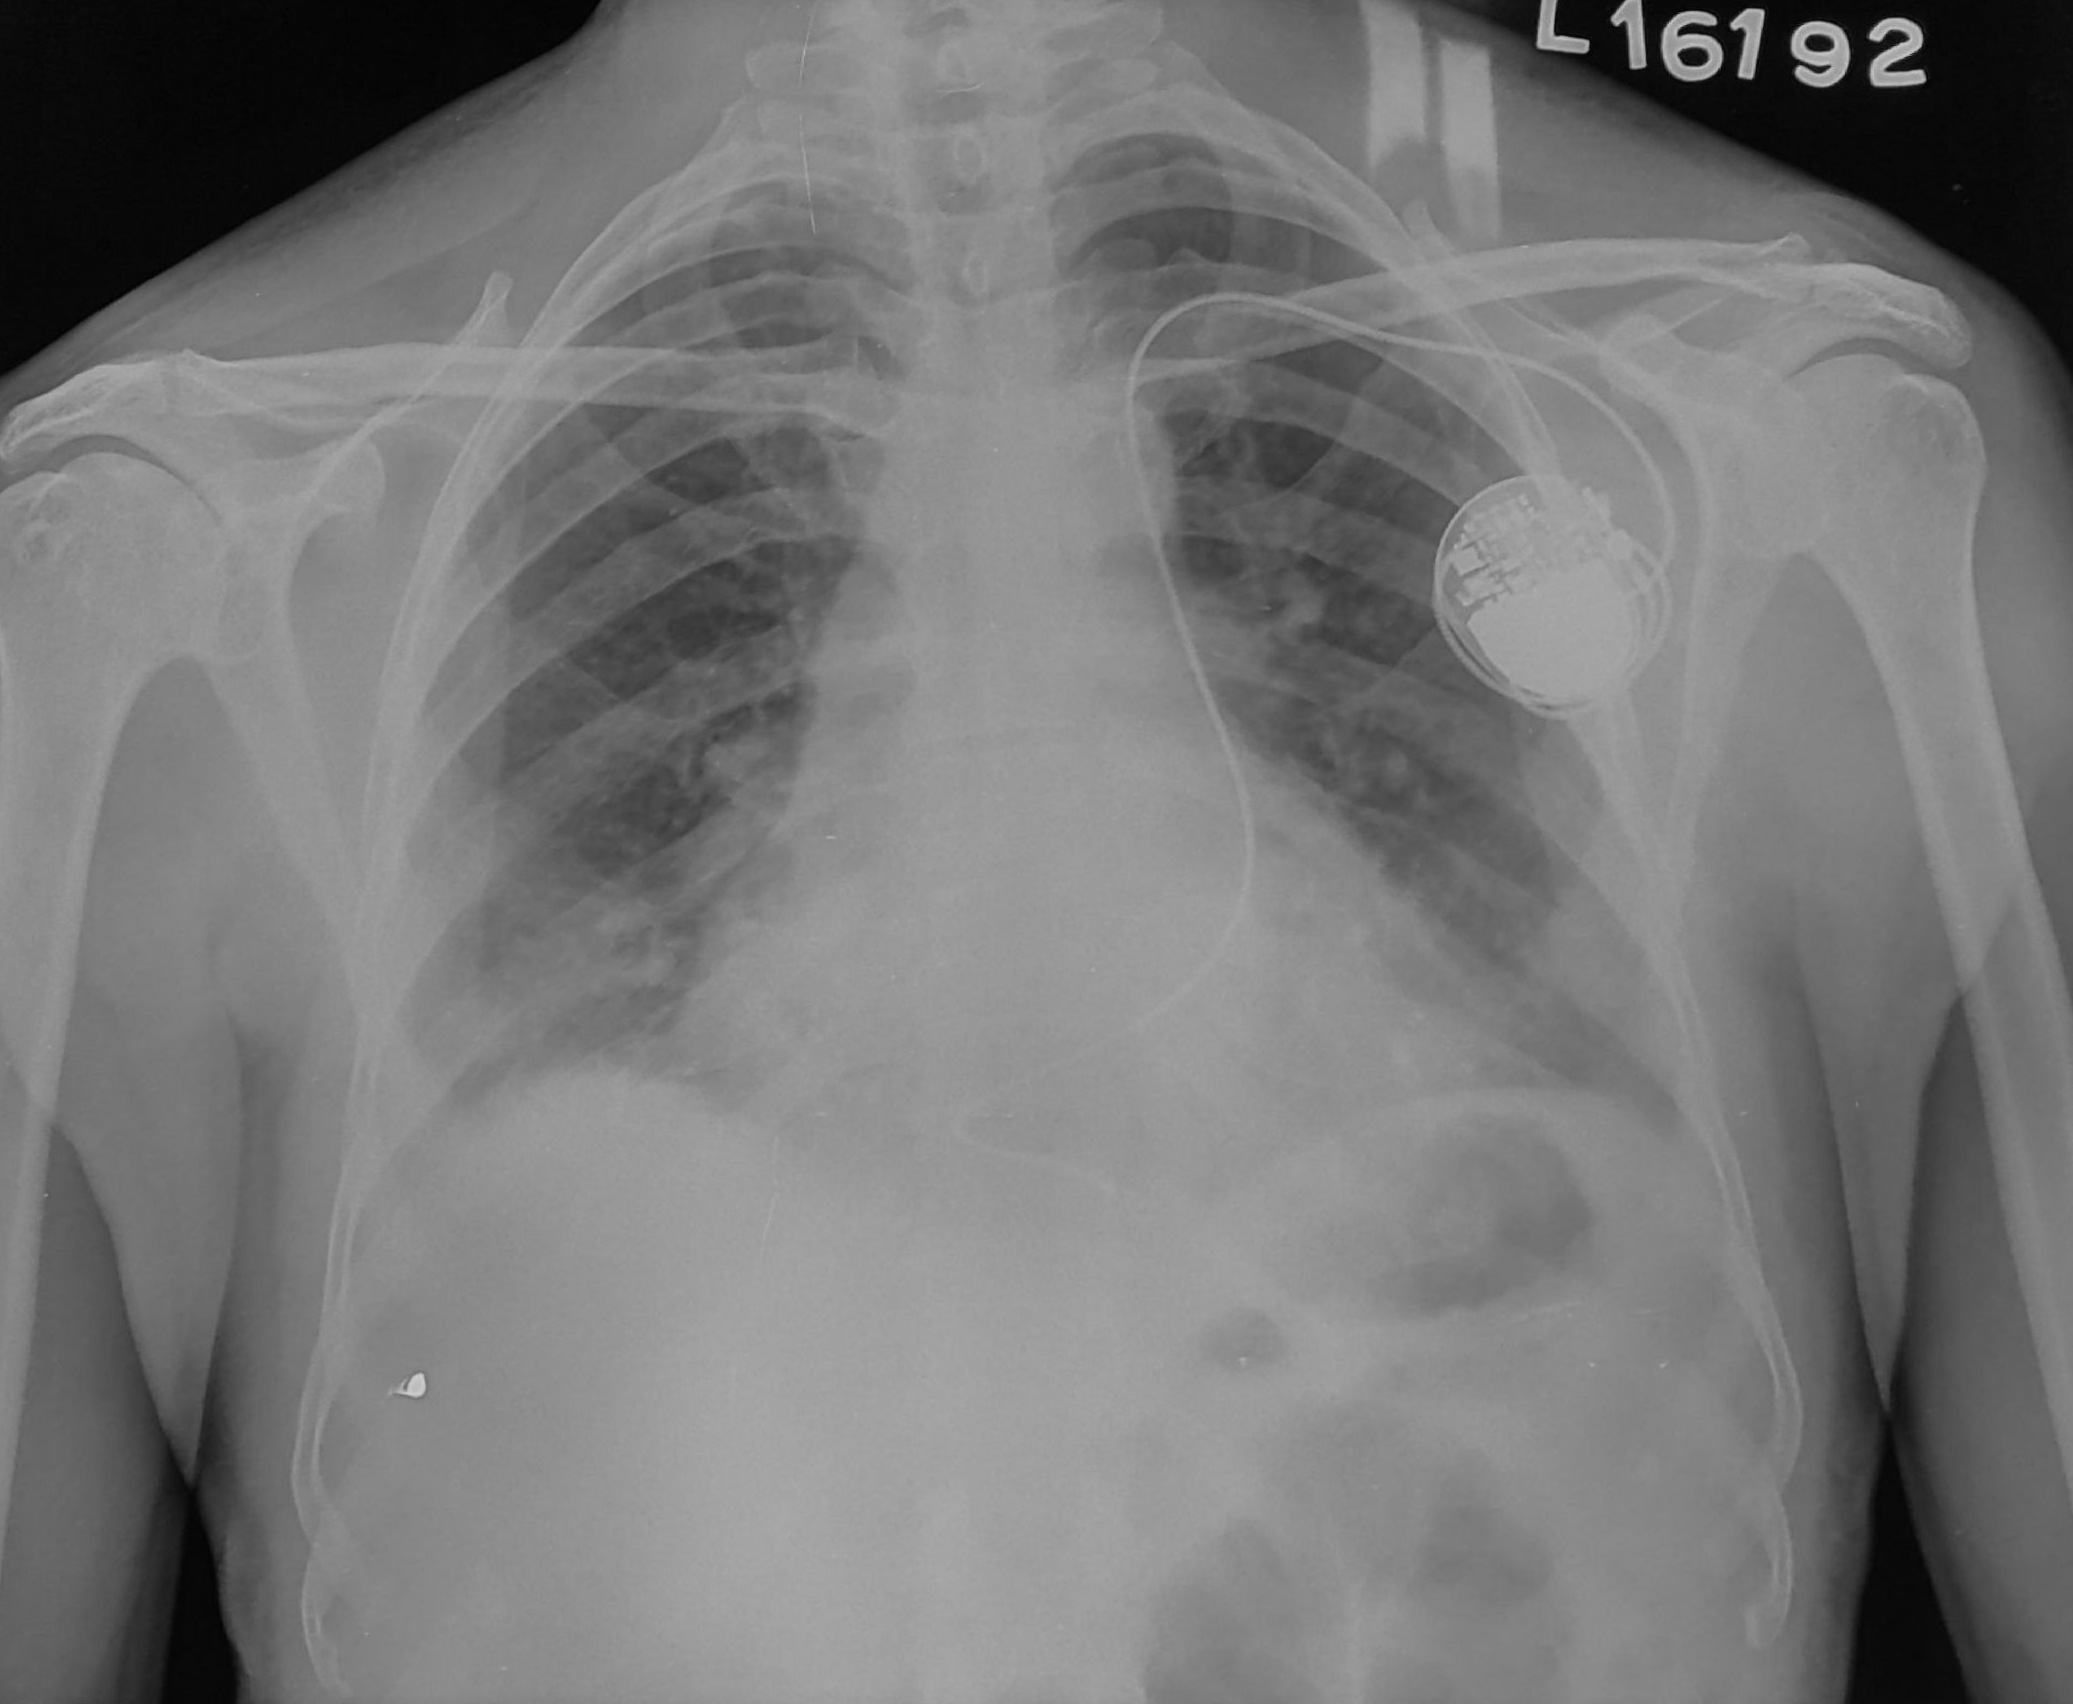

Post procedure CXR

pneumothorax_post_ppm.jpg